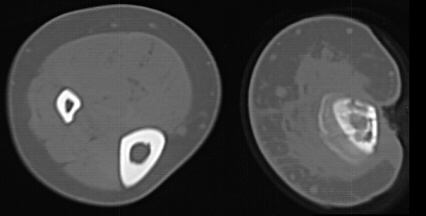

The patient presented to A.I. DuPont 15 days later (103 days after injury) with serosanguinous drainage from the upper portion of his lateral wound. Irregular areas of sclerosis and lucency of the tibia on plain films and CT as well as irregular uptake on bone scan suggested areas of necrotic bone and chronic osteomyelitis. A hand film showed a bone age of 17 and scanogram documented a 2 cm leg length discrepancy. A lateral cortical tibial sequestrum gradually demarcated. He was followed for a year without lasting resolution of his drainage and underwent sequestrectomy and open packing of the wound.